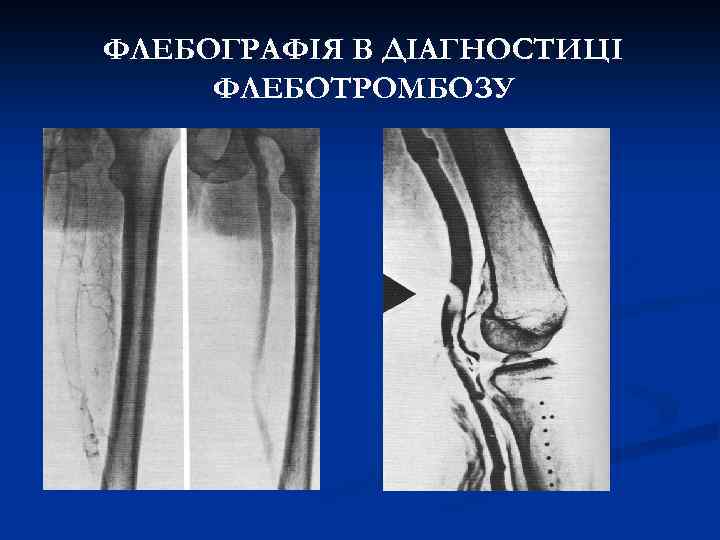

ФЛЕБОГРАФІЯ В ДІАГНОСТИЦІ ФЛЕБОТРОМБОЗУ

АЛГОРИТМ ДІАГНОСТИКИ ФЛЕБОТРОМБОЗУ 1. ДУМАТИ ПРО ФЛЕБОТРОМБОЗ У НЕЯСНИХ ВИПАДКАХ. 2. КЛІНІЧНЕ ОБСТЕЖЕННЯ. 3. ЛАБОРАТОРНІ ТЕСТИ ( Д-димери , коагулограма ) 4. ІНСТРУМЕНТАЛЬНІ ОБСТЕЖЕННЯ (ультразвукове, флебографія, КТ-флебографія)